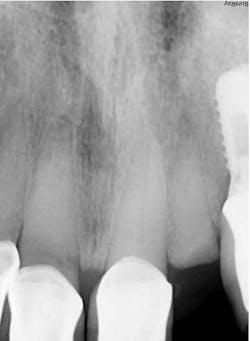

- Radiographic findings: Fractured lateral incisor with periapical pathology

- Implant: Ditron Ultimate 3.75 x 16 mm

- Abutment: Final straight 11.5 mm titanium abutment delivered at time of implant placement